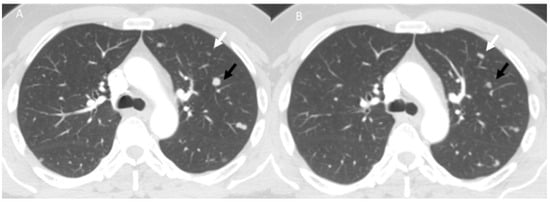

- Kalisz, K.R.; Ramaiya, N.H.; Laukamp, K.R.; Gupta, A. Immune Checkpoint Inhibitor Therapy-related Pneumonitis: Patterns and Management. Radiographics 2019, 39, 1923–1937. [Google Scholar] [CrossRef] [PubMed]

- Delaunay, M.; Cadranel, J.; Lusque, A.; Meyer, N.; Gounant, V.; Moro-Sibilot, D.; Michot, J.M.; Raimbourg, J.; Girard, N.; Guisier, F.; et al. Immune-checkpoint inhibitors associated with interstitial lung disease in cancer patients. Eur. Respir. J. 2017, 50, 1700050. [Google Scholar] [CrossRef]

- Kwak, J.J.; Tirumani, S.H.; Van den Abbeele, A.D.; Koo, P.J.; Jacene, H.A. Cancer immunotherapy: Imaging assessment of novel treatment response patterns and immune-related adverse events. Radiographics 2015, 35, 424–437. [Google Scholar] [CrossRef]

- Wang, G.X.; Kurra, V.; Gainor, J.F.; Sullivan, R.J.; Flaherty, K.T.; Lee, S.I.; Fintelmann, F.J. Immune Checkpoint Inhibitor Cancer Therapy: Spectrum of Imaging Findings. Radiographics 2017, 37, 2132–2144. [Google Scholar] [CrossRef]